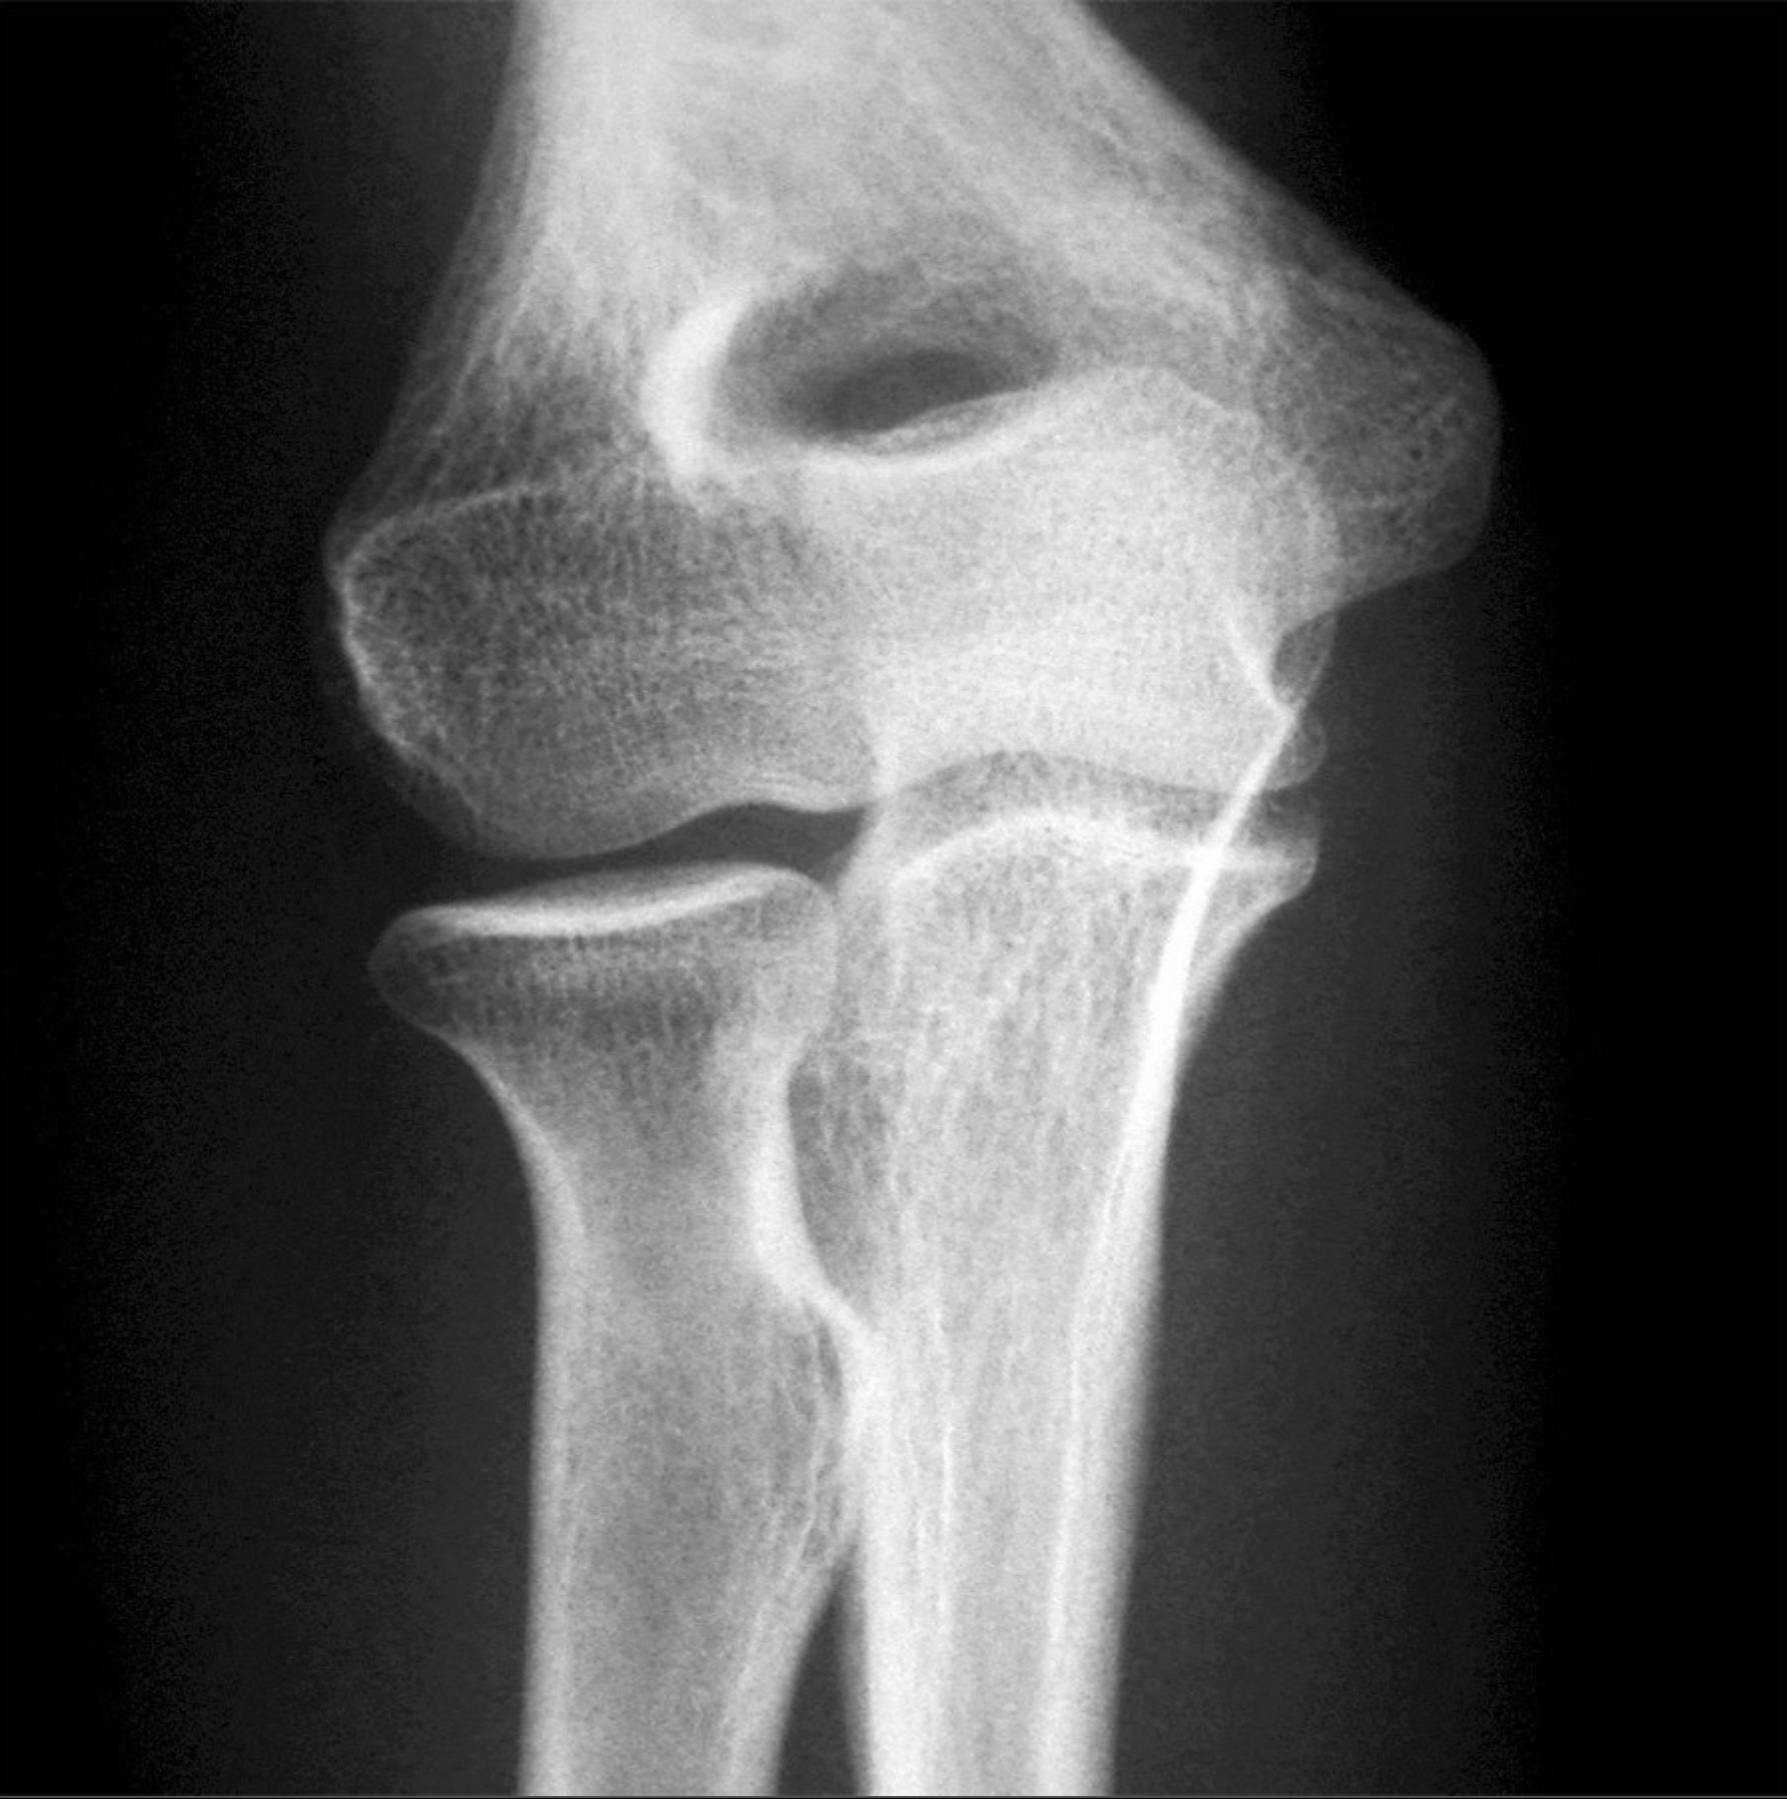

Lecture 29: Shoulder and Elbow Joints - Separation, Dislocation, Rotator Cuff Tear, Tommy John - M. Johnson

1. A shoulder separation and a shoulder dislocation occur at different joints. Review the anatomy of the acromioclavicular joint. Include bones, articulations, ligaments, capsules, cavities, movements and limitations of movement, and relationships.

3. The elbow joint consists of three joints: the humeroradial, humeroulnar, and proximal radioulnar joints. Review the anatomy of the elbow joint. Include bones, articulations, ligaments, capsules, movements and limitations of movements. Relate the anatomy of the medial ulnar collateral ligament to Tommy John surgery.

True/False. 1 Point Each.

11. On full flexion of the elbow, the coronoid process resides in the coronoid fossa and the radial head resides in the radial fossa. (True)

12. On full extension of the elbow, the olecranon process resides in the olecranon fossa. (True)

13. The lateral margins of the radial head articulates with the radial notch of the ulna. (True)

14. The head of the radius articulates with the capitulum of the humerus and the trochlear notch of the ulna articulates with the trochlea of the humerus. (True)

15. The medial collateral ligament of the elbow consists of anterior, posterior, and inferior bands (thickenings). (True)

16. The lateral collateral ligament of the elbow includes a radial collateral ligament and a lateral ulnar collateral ligament. (True)

17. The radial collateral ligament blends with the annular ligament. (True)

18. Supination and pronation occurs at the proximal radioulnar joint. (True)

19. The fiber direction of the interosseous membrane from high lateral (radius) to low medial (ulna) causes close-packing of the proximal radioulnar joint when there is proximal displacement of the radius. (True)

arrowbup Top arrowbdown Bottom